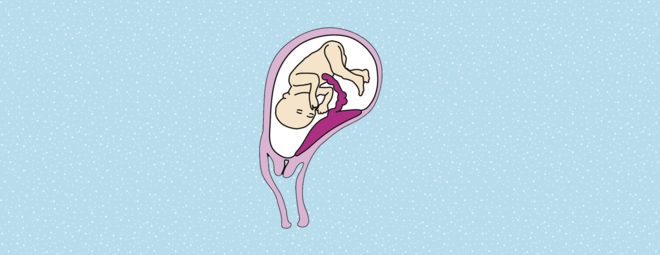

Warum wandert die Plazenta?

Manchmal liegt die Plazenta anfangs am Muttermund, am Ende der Schwangerschaft aber nicht mehr. Der Grund ist einfach:

Wo sitzt die Plazenta?

Die Lage des Mutterkuchens hat großen Einfluss darauf, ob ein Kind per Kaiserschnitt geholt werden muss. Je tiefer die Plazenta liegt, umso wahrscheinlicher ist der Eingriff